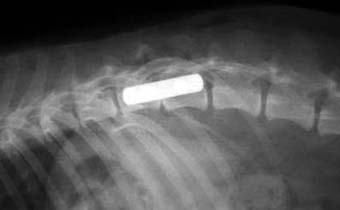

体重4kgの猫の脛骨骨幹部粉砕骨折。

ラグスクリューと細ピンによる骨片安定化とプレート固定術により整復固定しました。

写真上段: 手術前

骨幹部が縦に割れて多数の骨片に分かれています。

写真中段: 手術直後

骨片をラグスクリューと細ピンによりひとつにまとめてから、ほぼ全長にプレートをかけて固定しています。

写真下段: プレート除去後

ラグスクリューなどはそのままとなります。